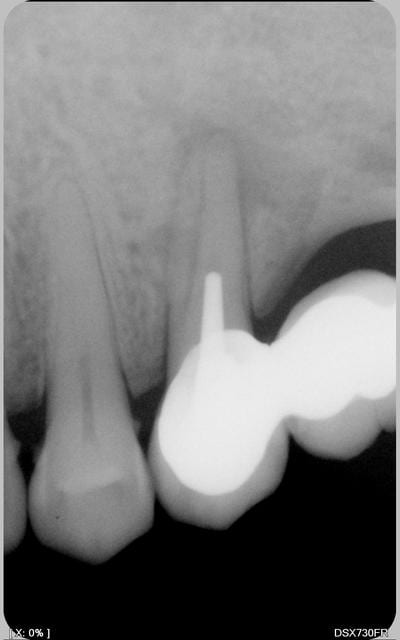

la radio.pas de poche paro

radio

reradio

gloups! apparemment tu n'as pu trouver qu'un seul canal.

Pas de possibilité de trouver le deuxième? Pas de lumière canalaire visible à la radio en tout cas.

Bon, sincèrement, suis pessimiste, ton cône dépasse pas mal de l'apex apparemment ou est-ce un artefact de la radio?

ce n'est pas un artefact et a mon sens, il n'y a pas de perf

apex ouvert

un seul canal arrivé à etre traité

dépassement apparent de cöne

je ne conserverai pas surtout en repilier de bridge

et donc implants à envisager

Azerty, je suis très pessimiste!

Le tenon originel était déjà dévié en direction de la furcation.

Il semble que lors de la reprise tu as poursuivi dans cette direction jusqu'à effraction dans le furcation.

Vu le rôle de pilier qui devrait échoir à cette dent, l'ensemble d'opérations qui consisterait à:

- reprendre le traitement au delà de la fausse route

- combler celle-ci au MTA

- cureter la furcation

- reconstituer le moignon par collage

me paraît un peu gonflé et le pronostic pour le moins réservé.

il n'y a qu'une seule solution_-l 'extraction.